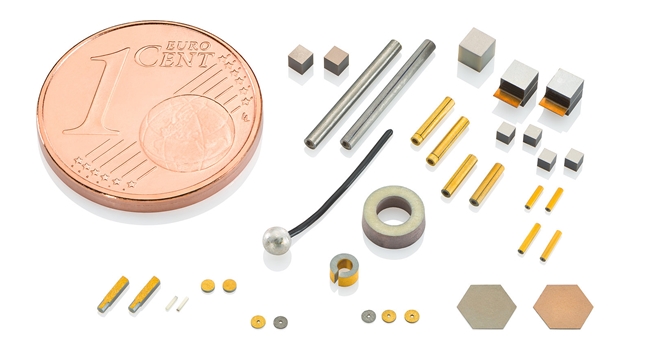

심혈관 질환은 심장마비나 뇌졸중과 같은 생명을 위협하는 합병증을 유발한다. 이를 해결하기 위한 방안으로 최소 침습적 카테터 솔루션이 적용되고 있다. 최소 침습적 카테터 솔루션은 부드러운 시술과 빠른 회복을 보장하므로 치료법으로 사용되고 있다. 피아이코리아는 이 솔루션을 성공시킬 방안으로 미니어처 피에조 소자 PI Ceramic을 소개했다.

동맥 경화증 또는 심장 부정맥과 같은 심혈관 질환은 전 세계 수백만 명의 사람들이 앓고 있으며 심장마비나 뇌졸중과 같은 생명을 위협하는 합병증을 유발한다. 이와 관련 피아이코리아(PI Korea)가 가장 작은 공간에서 비접촉적이고 최소 침습적인 치료에 적합한 미니어처 피에조 소자 PI Ceramic을 제안했다.

동맥 경화증 또는 심장 부정맥과 같은 심혈관 질환에 사용되는 혈관 내 쇄석술은 피에조 구동 초음파 카테터를 기반으로 한다. 이는 표적 병변의 도움을 받아 동맥 세동의 원인을 치료하거나 초음파로 경피적 대동맥판막 치환술(TAVI, TAVR)을 위한 치료 영역을 준비하거나 혈관 내 또는 대동맥 플라크를 비접촉적으로 파괴하는 데 사용된다. 이를 위해 안정적이고 효율적이면서 초소형인 기기가 필요하다. 작은 피에조 컴포넌트는 도구를 안정적으로 구동하고 부드러우면서 효과적인 치료를 가능하게 한다.